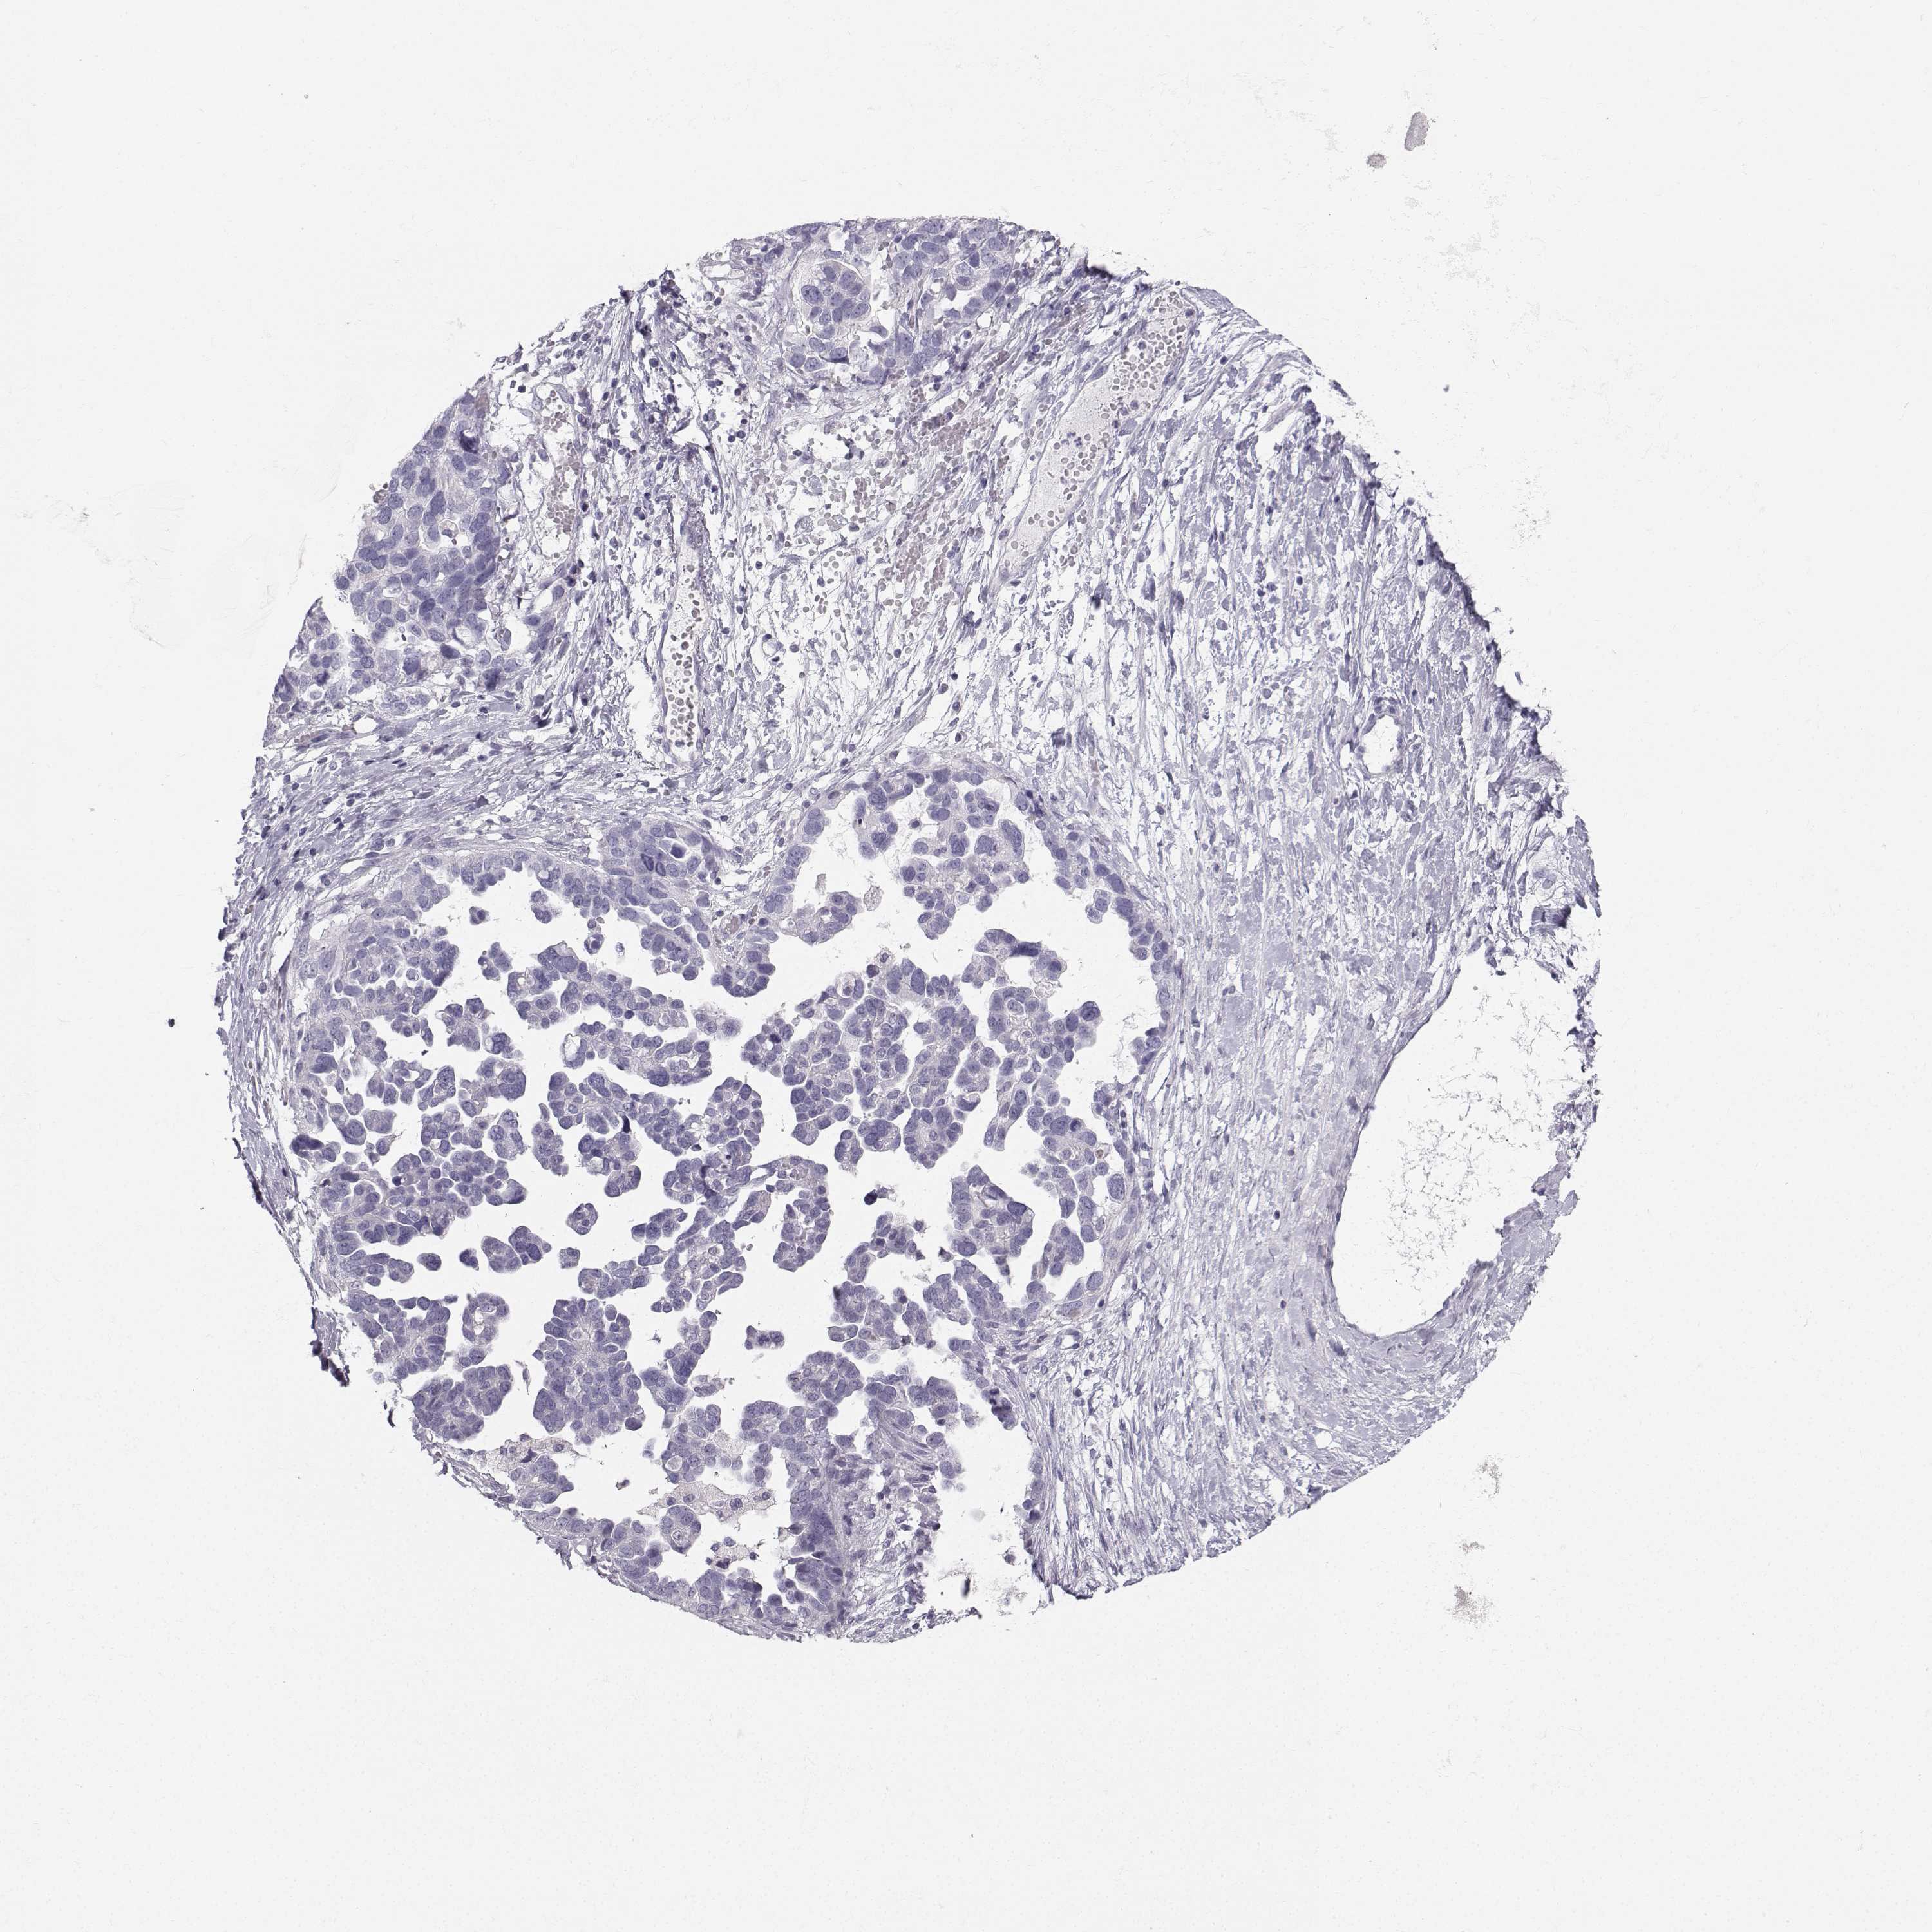

OVARIAN CANCER - Protein expressioni

A mouse-over function shows sample information and annotation data. Click on an image to view it in a full screen mode. Samples can be filtered based on level of antibody staining by selecting one or several of the following categories: high, medium, low and not detected. The assay and annotation is described here.

Note that samples used for immunohistochemistry by the Human Protein Atlas do not correspond to samples in the TCGA dataset.

Antibody stainingi

Antibody staining in the annotated cell types in the current human tissue is reported as not detected, low, medium, or high, based on conventional immunohistochemistry profiling in selected tissues. This score is based on the combination of the staining intensity and fraction of stained cells.

Each image is clickable and will lead to virtual microscopy that enables deeper exploration of all samples and also displays staining intensity scores, fraction scores and subcellular localization as well as patient and tissue information for each sample.

Antibody HPA055162

Staining

High

Medium

Low

Not detected

Intensity

Strong

Moderate

Weak

Negative

Quantity

>75%

75%-25%

<25%

None

Location

Nuclear

Cytoplasmic/membranous

Cytoplasmic/membranous,nuclear

Cystadenocarcinoma, serous, NOS

Cystadenocarcinoma, mucinous, NOS

Carcinoma, endometroid